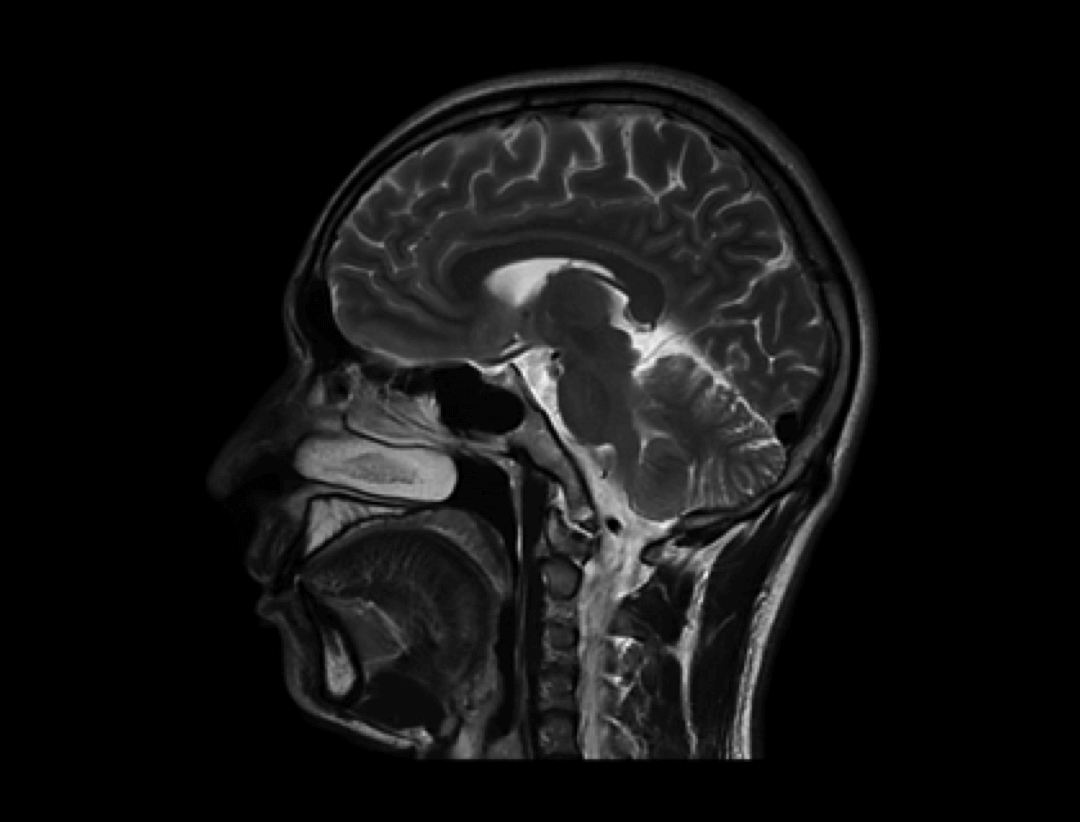

智云平台

智云磁体

自主研发的匀场技术,优异的磁场均匀度。

智云梯度

智能涡流补偿技术,高梯度性能。